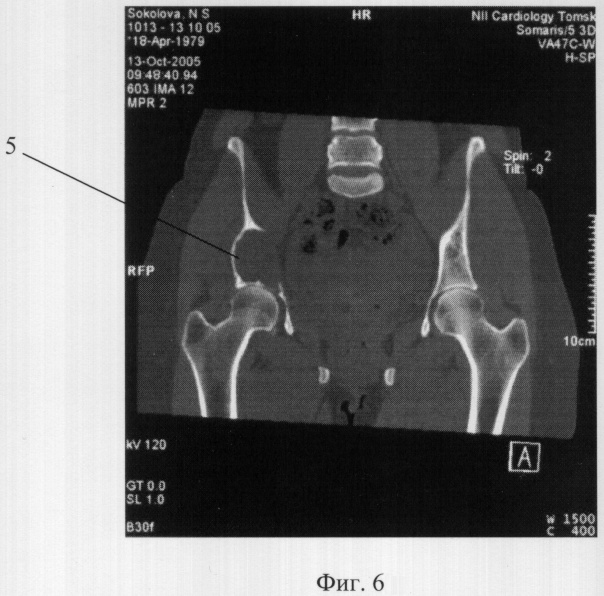

Фиг.6. Рентгенограмма дефекта вертлужной впадины тазобедренного сустава больной. 5 – отсутствующий участок.

В положении больной на спине осуществлен подвздошный доступ к крылу и телу тазовой кости. Ревизией полости выявлено: тело кости вздуто опухолью бурого цвета. Срочное исследование новообразования и его границ с нормальной костью уточнили картину патологии. Злокачественных клеток не обнаружено. Дистальный участок суставной поверхности вертлужной впадины, примерно площадью 4 см2, отсутствует (5 фиг.6). Зияет головка бедренной кости. Разрушено, на участке, внутреннее кольцо таза; имеется его патологическая подвижность.